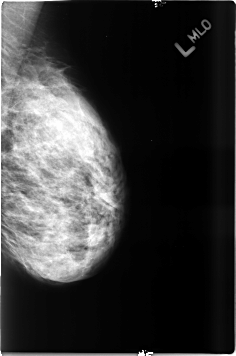

B_3485_1.LEFT_MLO

LEFT_MLO LINES 4624 PIXELS_PER_LINE 3056 BITS_PER_PIXEL 12 RESOLUTION 50 NON_OVERLAY